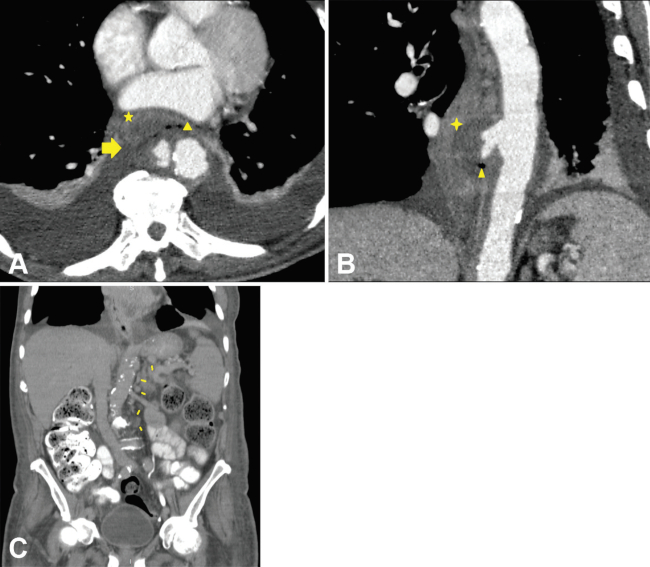

Pseudoaneurisma micótico

Con el término “micótico” se hace referencia a los aneurismas que son ocasionados por un proceso infeccioso. Es altamente infrecuente (prevalencia de 0,06% a 2,6%) y potencialmente fatal si no es tratado a tiempo.1

Son consecuencia de una infección que debilita la pared formando una falsa luz o pseudoaneurisma. La localización más común es la aorta infrarrenal, seguida de la aorta descendente y el patógeno mayormente implicado es Salmonella.

En la TCMD, se observan aneurismas con forma sacular en 90% de los casos y gas perianeurismático. Puede llegar a encontrarse destrucción vertebral, abscesos en el músculo psoas e infartos renales (►Fig. 6 and 7).1